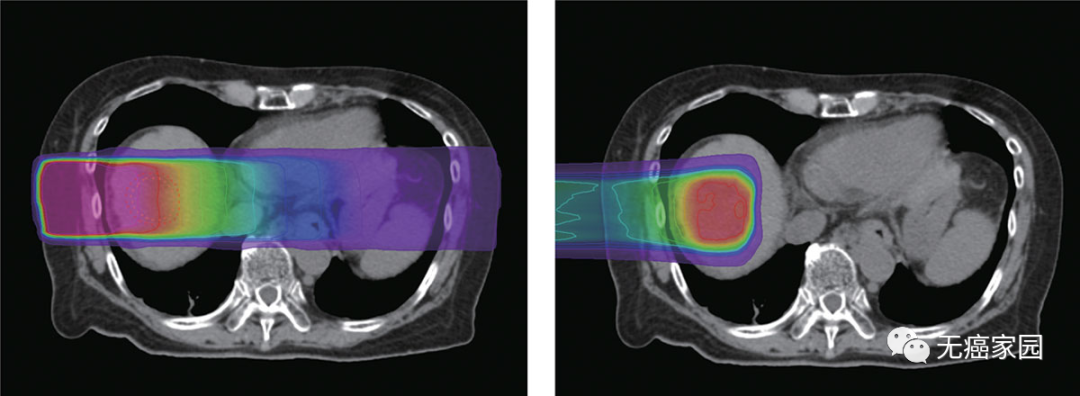

X射线(左)在皮肤附近提供最大剂量的辐射,并在它们离开身体进入肿瘤时逐渐失去能量。相反,质子束(右)在肿瘤周围释放其大部分抗癌能量,然后立即停止。